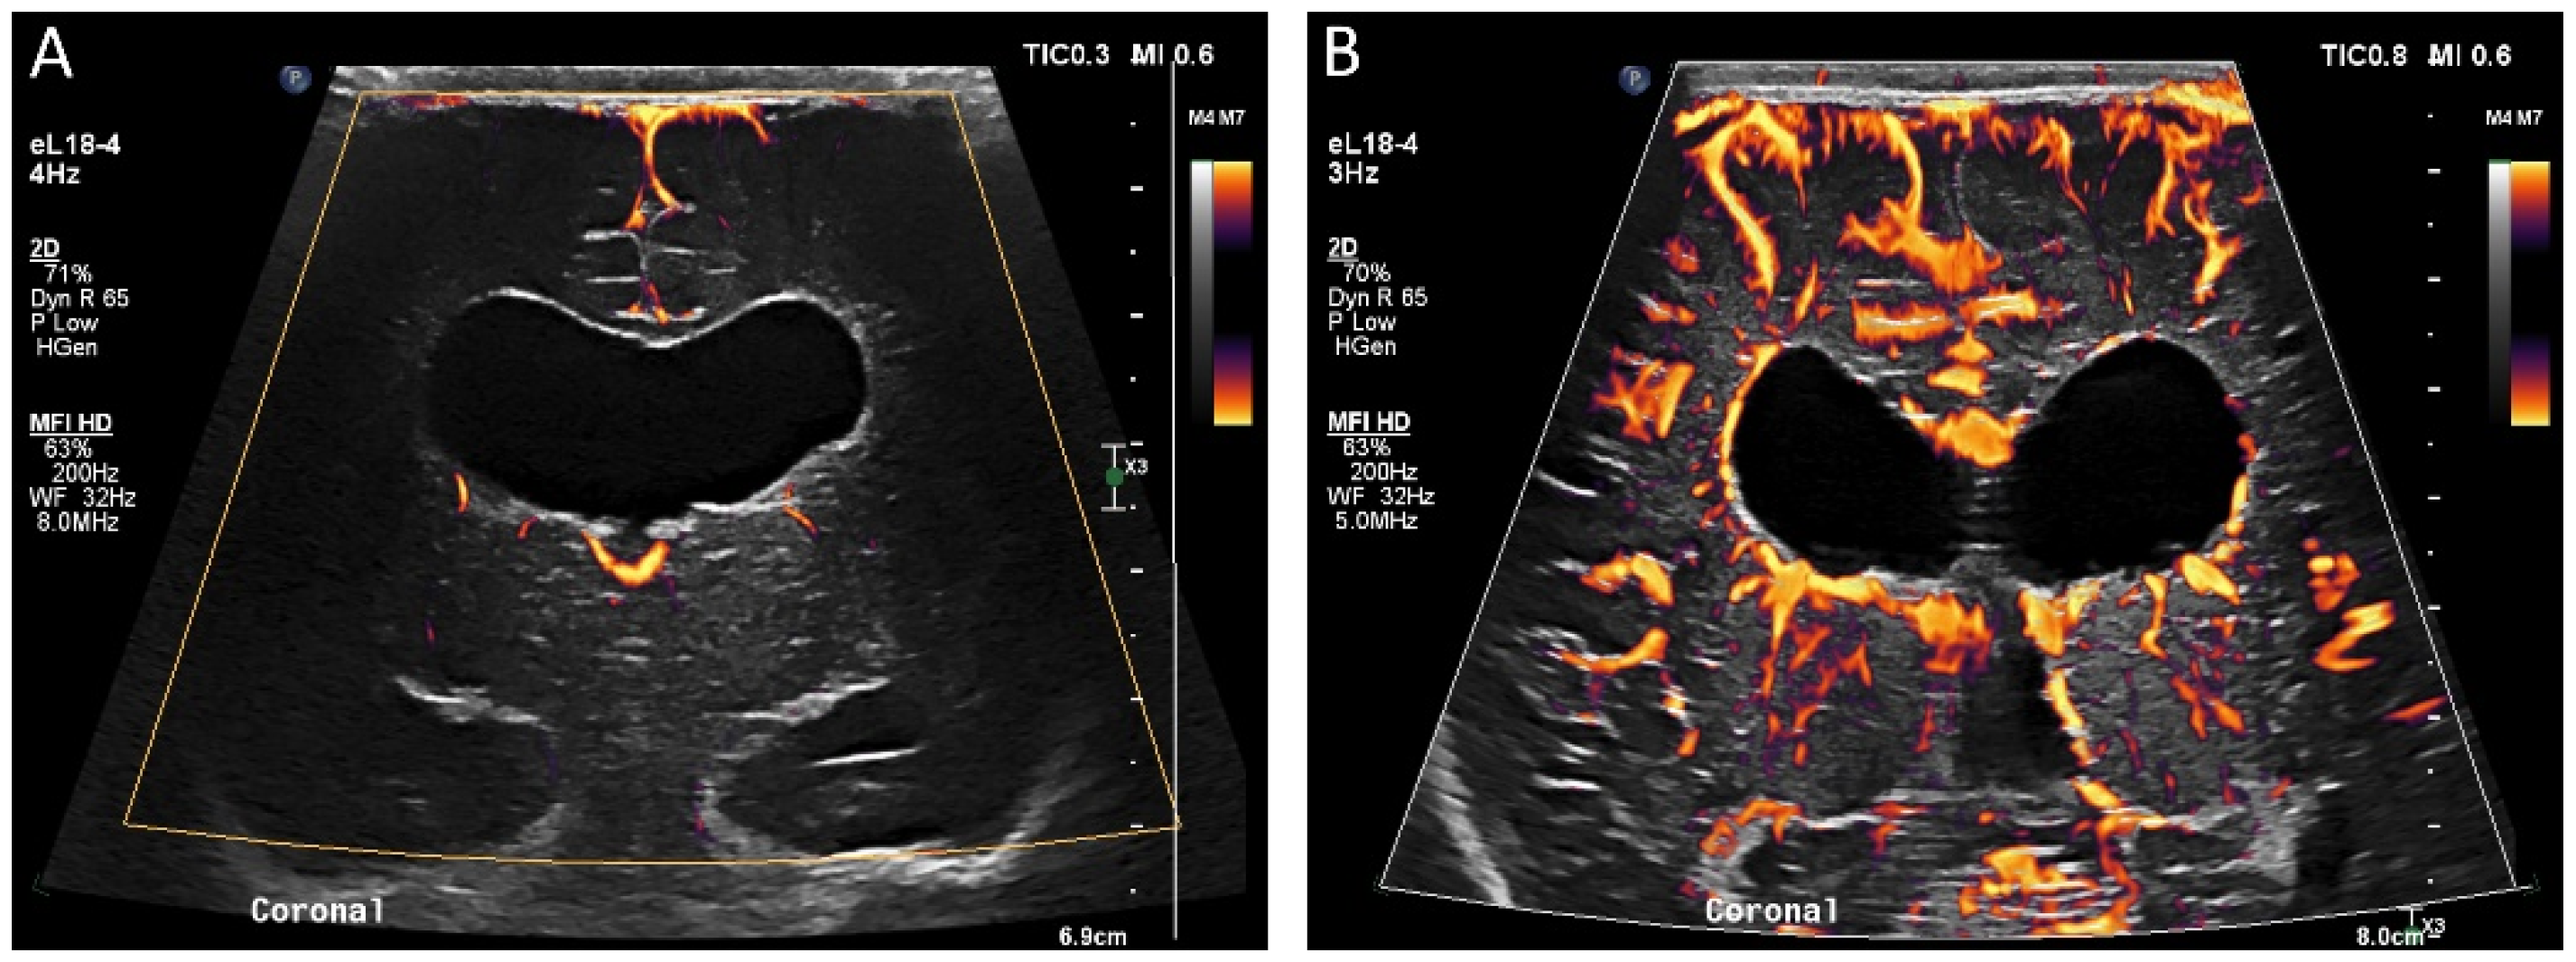

The use of MVI in the brain is in its early experimental stages. The few studies examining this proposed use of MVI demonstrate high inter-reader reliability for determining the presence of superficial and deep microvessels and depicting functional alterations in the brain with pathologic implications otherwise unavailable on grayscale ultrasound [42,43] (Figure 5 and Figure 6). Like on CEUS, changes in perfusion associated with ischemia may be visualized by MVI [43]. Furthermore, the detectability of superficial microvessels increases with gestational age in preterm infants, potentially allowing for evaluation of brain maturity [43]. In one study in older adults, MVI showed promise in the detection of acute ischemic stroke with reduced vascularity in areas of ischemia [44]. In instances of intraparenchymal intracranial hemorrhage, MVI may be used to delineate the margins of the hemorrhage, with acute blood products being avascular or hypovascular relative to normal brain tissue [45]. In addition to identifying the absence of microvasculature, MVI can demonstrate abnormal or increased microvascular perfusion, such as in the detection of abnormal vessels in brain tumors [46].

Figure 5.

(A) Ultrasound with color microvascular imaging in a 6 day old, former 32 week 2 day infant with multiple congenital anomalies including absence of the septum pellucidum. Overall reduced cortical and deep gray nuclei microvascular flow is observed. (B) Ultrasound with color microvascular imaging of a 51 day old, former term infant with congenital hydrocephalus. Overall increased microvascular perfusion is seen throughout the cortex, white matter, and deep gray matter compared to the infant in (A). The significance of these and similar findings has yet to be elucidated and may be of import for clinical management and prognostication.

Figure 6.

(A) Grayscale and (B) color microvascular imaging ultrasound a 13 day old, former 33 week 5 day infant with congenital heart disease and hypoxic respiratory failure on extracorporeal membrane oxygenation with seizures. Elevated flow is seen within the deep gray matter. This may reflect perfusion alterations in the setting of seizure, dysfunctional autoregulation, and/or evolving injury.